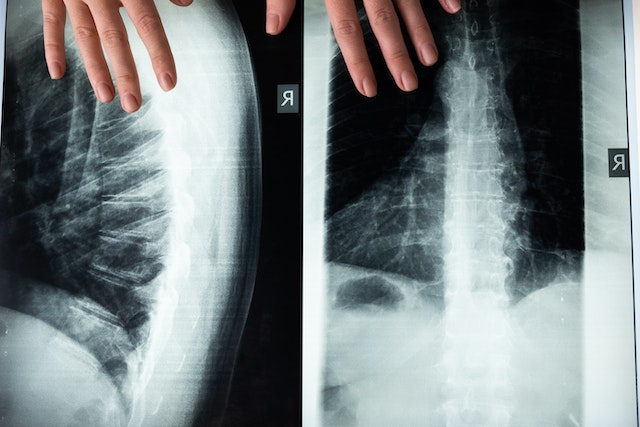

1) 골다공증의 진단은 골밀도 검사로 할 수 있습니다. 골밀도 검사는 뼈의 양을 측정하는 검사로, X-선을 이용하는 DXA 방법이 가장 정확하고 널리 사용됩니다.

2) 골밀도 검사 결과는 T 점수라는 수치로 나타내는데, 이는 건강한 젊은 성인의 평균 골밀도와 비교한 차이를 표준편차 단위로 나타낸 것입니다. T 점수가 -1 이상이면 정상, -1 ~ -2.5 사이면 골감소증, -2.5 이하면 골다공증으로 분류됩니다.